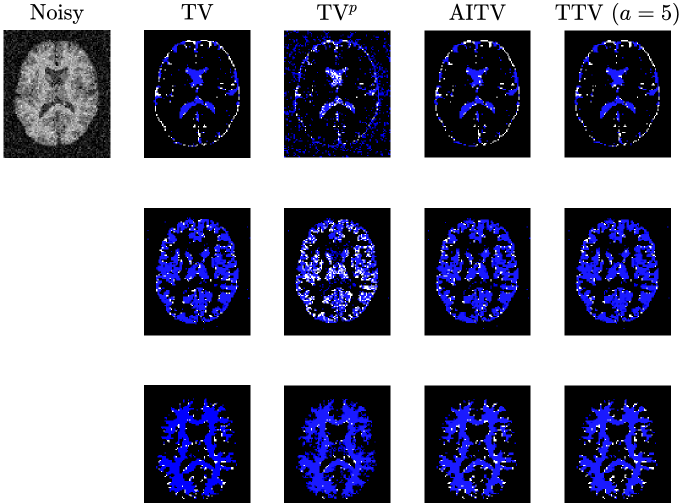

Refer to caption

(a) Vessel 1

(b) Vessel 2

Figure 2: Segmentation results of Figures 1(a)-1(b) (after normalization) corrupted by Gaussian noise of mean 0 and variance 0.01.

Before applying the segmentation algorithms, the images in Figure 1 are normalized to [0,1]01[0,1][ 0 , 1 ] followed by Gaussian noise corruption. The retina vessel images are corrupted with Gaussian noise of mean 0 and variance 0.01. Table I reports the performances and times of the segmentation methods on the retina vessel images while Figure 2 shows some of their results. TTV (a=10,100)𝑎10100(a=10,100)( italic_a = 10 , 100 ) has the highest DICE and Jaccard similarity indices across the three images although requiring about 80 seconds to complete, thereby being slower than TV and TVp. The brain images are corrupted with Gaussian noise of mean 0 and variance 0.04. Table II reports the performances and times of the multiphase segmentation, while Figure 3 shows the segmentation results of Figure 1(g). By its DICE and Jaccard similarity indices, TTV (a=1)𝑎1(a=1)( italic_a = 1 ) is best at segmenting CSF across the four images while TTV (a=5,10)𝑎510(a=5,10)( italic_a = 5 , 10 ) remains competitive against AITV in segmenting GM and WM. On average, TTV (a=1,5)𝑎15(a=1,5)( italic_a = 1 , 5 ) is among the top two best-performing methods. Although it can be outperformed by AITV, it is at least three times faster. In Figure 3, we see that TTV (a=5)𝑎5(a=5)( italic_a = 5 ) is most effective in segmenting CSF, especially compared to TV and TVp. Moreover, comparable to TV and AITV, it is able to identify most of the GM and WM regions. Overall, using TTV, the proposed method is able to effectively identify narrow, thin regions such as the retina vessels and CSF.